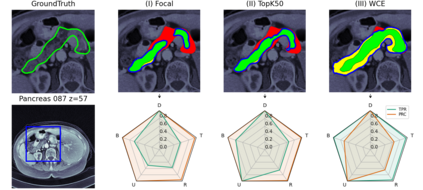

Manual segmentation of medical images (e.g., segmenting tumors in CT scans) is a high-effort task that can be accelerated with machine learning techniques. However, selecting the right segmentation approach depends on the evaluation function, particularly in medical image segmentation where we must deal with dependency between voxels. For instance, in contrast to classical systems where the predictions are either correct or incorrect, predictions in medical image segmentation may be partially correct and incorrect simultaneously. In this paper, we explore this expressiveness to extract the useful properties of these systems and formally define a novel multi-modal evaluation (MME) approach to measure the effectiveness of different segmentation methods. This approach improves the segmentation evaluation by introducing new relevant and interpretable characteristics, including detection property, boundary alignment, uniformity, total volume, and relative volume. Our proposed approach is open-source and publicly available for use. We have conducted several reproducible experiments, including the segmentation of pancreas, liver tumors, and multi-organs datasets, to show the applicability of the proposed approach.